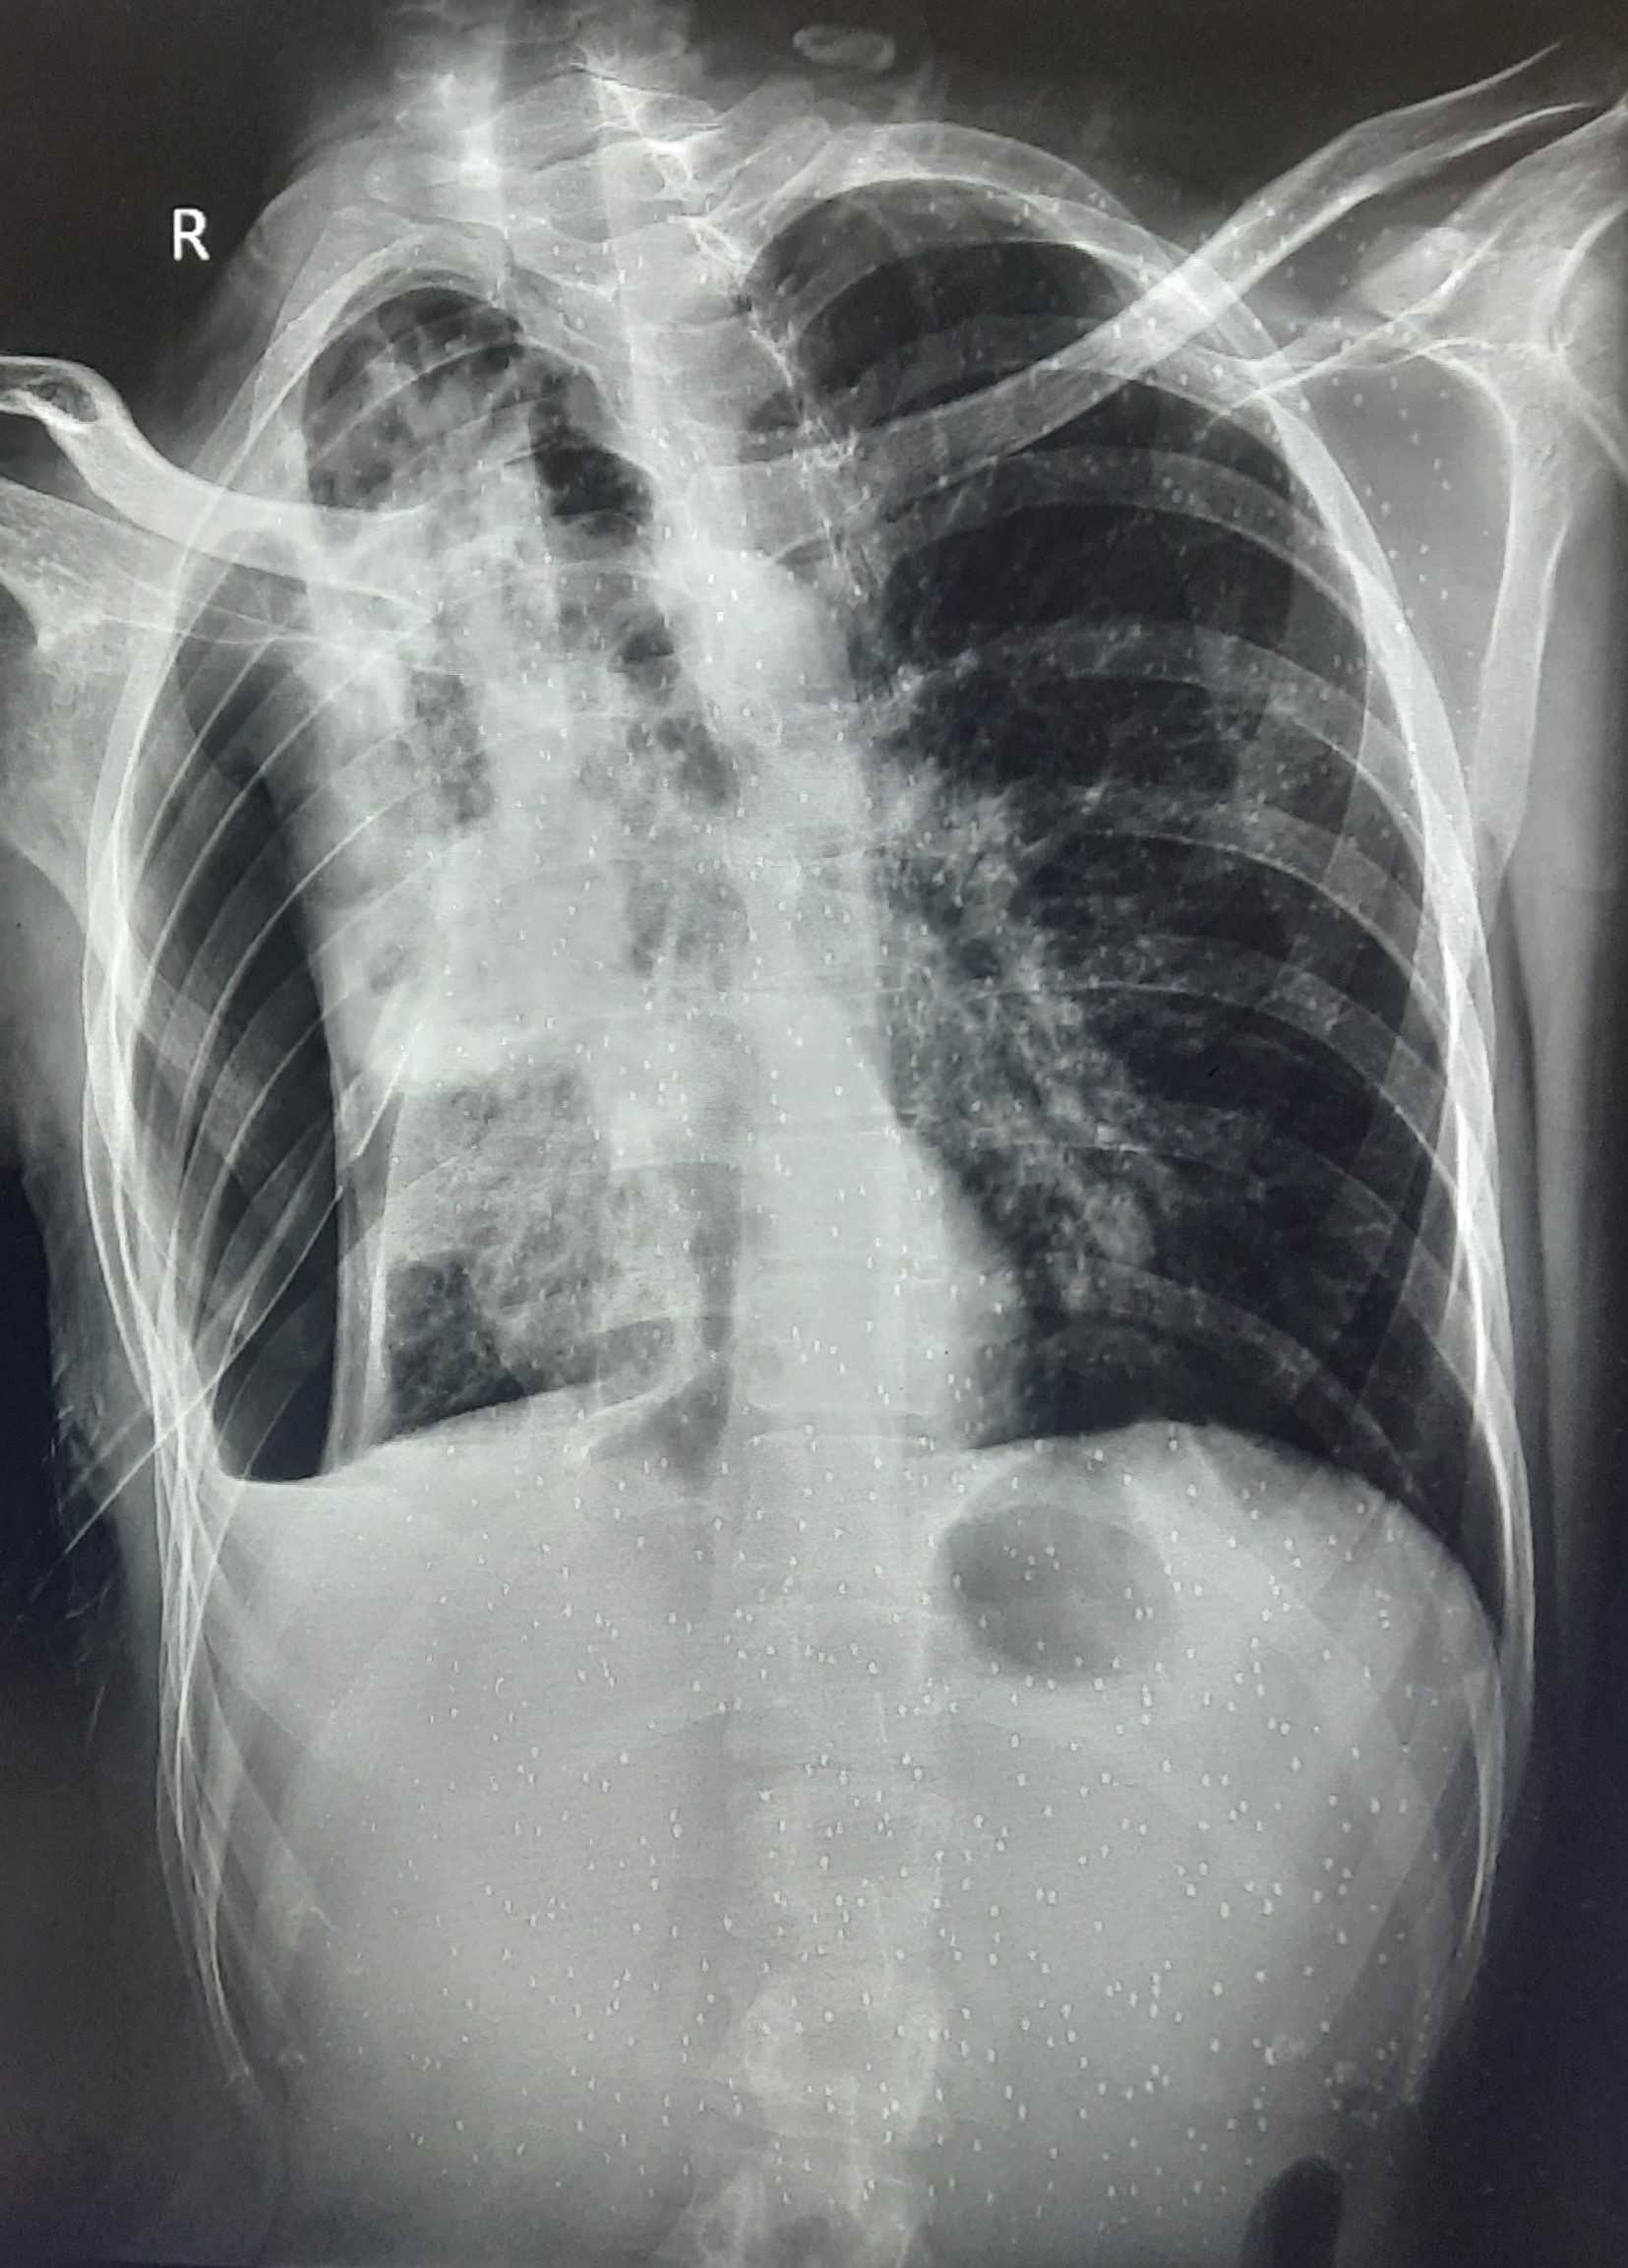

| 213 | IGGMC, Nagpur, Nagpur | P2 | 29-4259 | NARENDRA YADAV | Consent taken on Paper | 42 Yrs. |

Provisional Diag : Rt. SIDED LOCULATED PNEUMOTHORAX WITH Lt. ICD IN SINCE (15/11/24)

Final Diag : CLINICALLY DIAGNOSED TUBERCULSIS PLEURAL EFFUSION ON ATT (17/11/24) |

TB Case (Confirmed) | CXR: Rt. SIDED LOCULATED PNEUMOTHORAX Rt. U2+M2+L2 AND Lt. M2 CONSOLID? | Abnormality visible on x-ray |